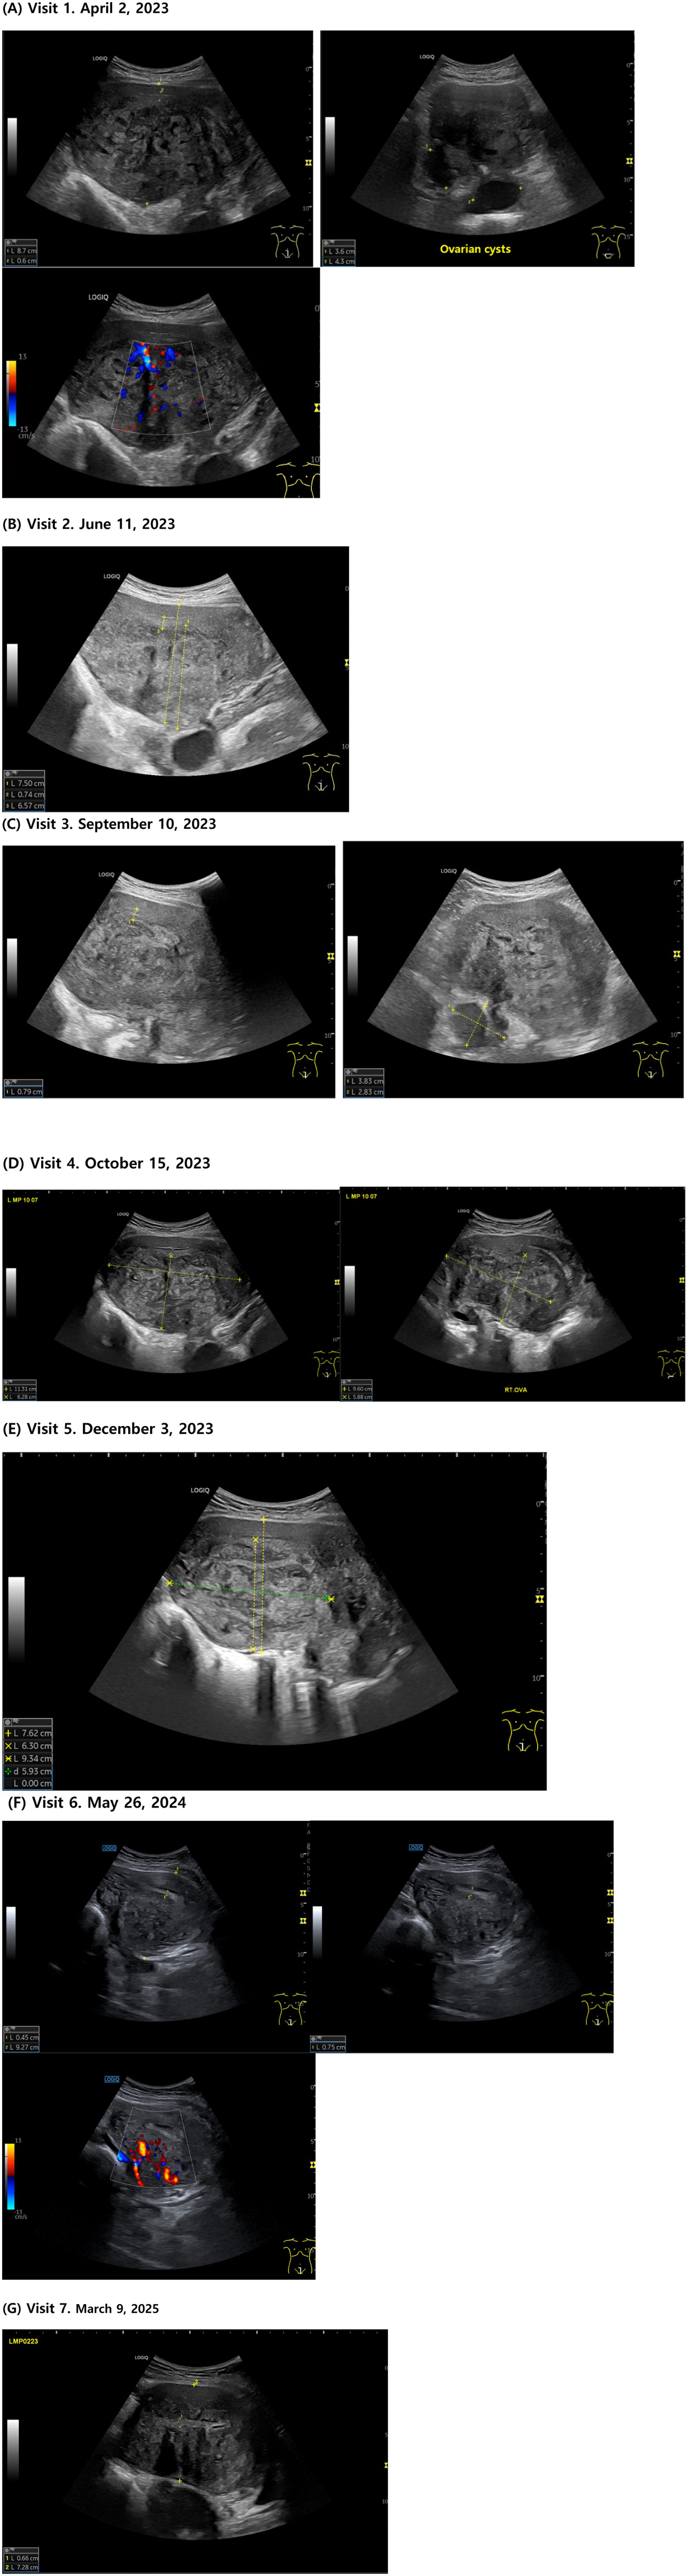

Figure 2. Transabdominal ultrasound images showing adenomyosis. (A) Visit 1. April 2, 2023. (B) Visit 2. June 11, 2023. (C) Visit 3. September 10, 2023. (D) Visit 4. October 15, 2023. (E) Visit 5. December 3, 2023. (F) Visit 6. May 26, 2024. (G) Visit 7. March 9, 2025.

On the day of her visit, ultrasonography revealed a globally enlarged uterus with asymmetric thickening of the myometrium. According to MUSA 2022, multiple direct signs were seen, including myometrial cysts, hyperechoic islands, and echogenic subendometrial lines and buds. Indirect signs included asymmetrical myometrial thickening, fan-shaped shadowing, and translesional vascularity on color Doppler. The presence of direct and indirect signs supported a diagnosis of adenomyosis per MUSA guidelines.

The patient had severe menstrual pain, anemia, indigestion, and dizziness at the time of her first visit (April 2, 2023 [LMP; March 25, 2023]), making it difficult for her to carry out daily life activities to the point where she had to lie down for approximately 2 weeks out of the month. Her menstrual cycle was short (24–25 days) and an ultrasound examination showed that most of the posterior wall of the uterus was filled with adenomyotic tissue and the uterine anteroposterior (AP) length was 8.7 cm. Her EQ-5D-5L index was 0.288 points and her NRS score was 7–8.

On June 11, 2023, after 6 weeks of taking the herbal medicine, the patient’s menstrual pain decreased to NRS 4–5, and the dosage of painkillers was reduced to 1–2 daily for only 2 days when the pain was severe. The intensity and frequency of back pain also decreased, and small meals and sleep were possible even on days when the menstrual pain was severe. The uterine AP length was 7.5 cm.

During gynecological examination in late August 2023, the patient’s hemoglobin level improved to 10.4, and ultrasound findings indicated regeneration of normal myometrial tissue, starting from the margins of the adenomyotic lesion.

On October 15, 2023 (LMP; October 7, 2023), the menstrual cycle gradually became longer, and ultrasound findings showed that the boundary between the adenomyotic lesion and the endometrium had become clearer, with an expansion of normal endometrial tissue and a reduction in the size of the ovarian cysts.

On December 3, 2023 (LMP; November 21, 2023), an ultrasound examination revealed a decrease in the extent of adenomyotic lesions and an increase in the extent of normal tissue. The uterine AP length was 7.62 cm. In addition, during a health checkup conducted in the same month, the hemoglobin level normalized to 11, and during a gynecological examination in February 2024, both the size of the ovarian cysts and the extent of adenomyosis had decreased.

By May 26, 2024 (LMP; May 10, 2024), the menstrual cycle had normalized to 28–29 days, the menstrual period lasted 4–5 days, and the menstrual flow decreased to a point where only 5–6 large sanitary pads were used for 2–3 days of heavy menstrual flow. No clots or flooding were observed, and the PBAC score was approximately 55, which is within the normal range. Menstrual pain was greatly reduced to NRS 1–2, and the number of painkillers used was reduced to 1–2. The degree and duration of back pain also significantly reduced, and normal eating and activities of daily living were possible even during menstruation. Secondary symptoms such as dizziness, decreased physical strength, and indigestion also significantly improved, and normal activities of daily living were possible, unlike before when she had to lie down for more than half a month. In addition, ultrasound according to MUSA 2022 showed myometrial cysts and hyperechoic islands present but reduced in size and number; subendometrial echogenic lines and buds were not detected, with a distinct endometrium separate from the myometrium. The uterine anterior wall ratio was increased compared to before treatment, and atypical intramyometrial shadows decreased. Color Doppler revealed blood flow crossing the lesion at some distance from the junctional zone. The uterus remained asymmetrically enlarged but the fundus partially regained normal shape. The endometrium–myometrium junction was relatively regular with normal tissue pattern and continuous echoes, and the junctional zone thickness averaged 15 mm. The mean EQ-5D-5L index was 0.877 points, and she stopped taking herbal medicine thereafter. Changes in ultrasound findings based on the MUSA 2022 criteria are summarized in Supplementary Tables 1, 2. After discontinuation of herbal medication, the liver function test (AST 18 IU/L, ALT 6 IU/L, γ-GTP 6 IU/L) and renal function test (creatinine 0.6 mg/dL, eGFR 113 mL/min/1.73m²) were all within normal ranges.

On March 9, 2025 (LMP; February 23, 2025), the patient went on with her normal daily life activities with negligible menstrual pain; therefore, she did not require painkillers but remained on Yaz® oral contraceptive (half tablet). The uterine AP length was 7.28 cm. The EQ-5D-5L index was maintained at 0.877 points.